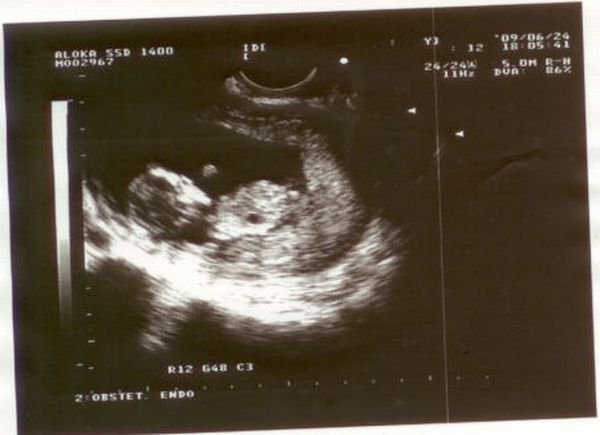

Szilardinho, jók a képek, és gratulálok az eredményhez is!

Uxi, túl sok mindent nem fogsz még látni. Ilyenkor még olyan kis ufók